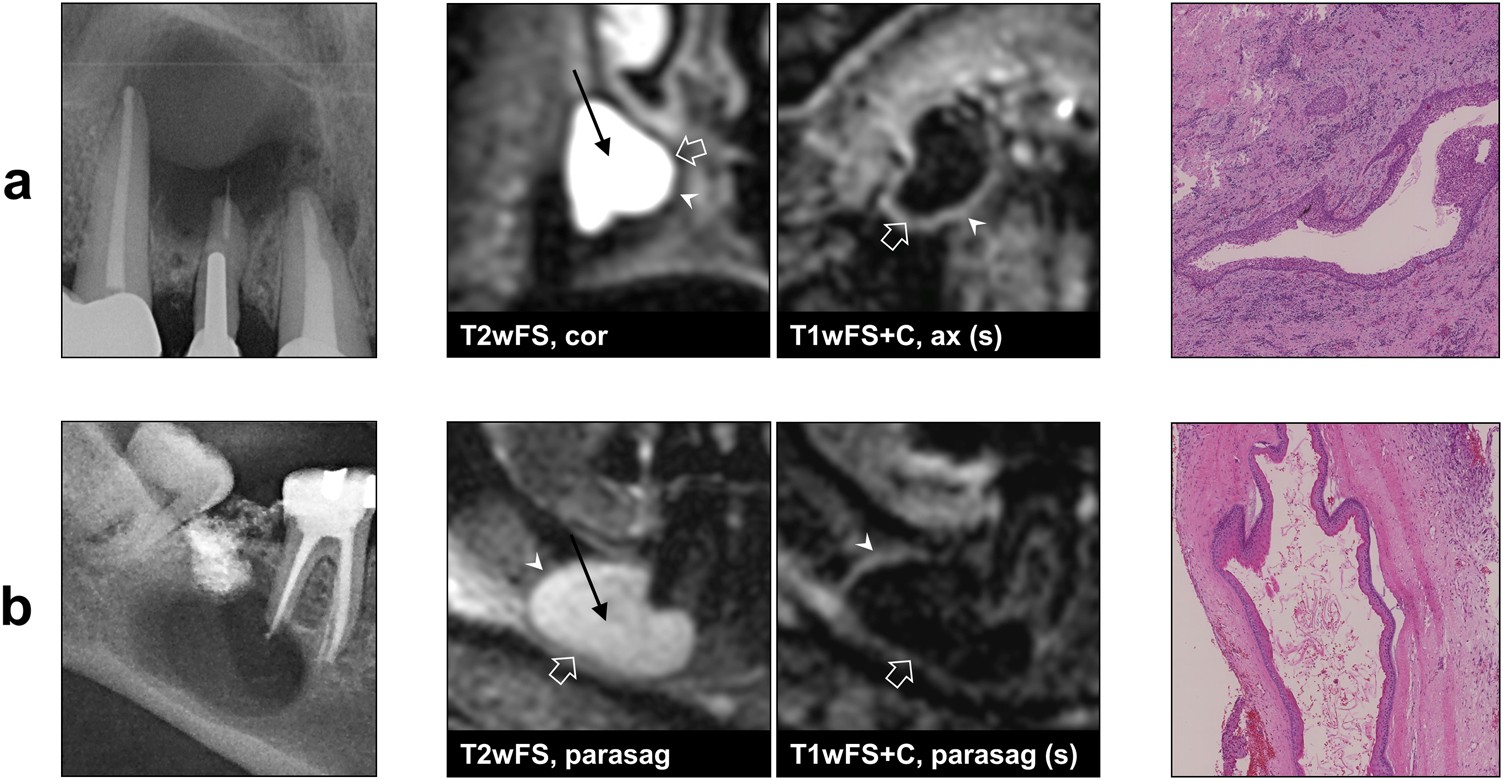

Fig. 4

From: Differentiation of periapical granulomas and cysts by using dental MRI: a pilot study

Example images of two periapical cysts (radiographs, dental MRI and histopathology). Histopathological results: a radicular cyst; b odontogenic keratocyst. On MRI, both cysts show a well-defined outer margin (arrow heads) without soft tissue involvement, a thin peripheral rim with a homogeneous contrast-enhancement in T1wFS+C (open arrows), and a homogeneous texture of the lesion center in T2wFS (straight arrows). Note the identical MRI features of the radicular cyst and the keratocyst. T2wFS T2- weighted with fat saturation, T1wFS+C T1-weighted with fat saturation+contrast agent, (s) subtraction, cor coronal, ax axial, parasag parasagittal